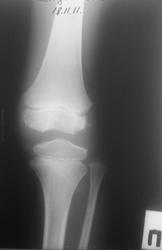

Мальчик 11 лет, жалобы на боли в коленных суставах в утреннее время. Движения в полном объеме, безболезненные, варусная деформация голеней с обеих сторон. У отца и деда выраженый гоноартроз.

Вопрос к детским рентгенологам (сама с детьми не работаю)-"лохматость" контуров суставных поверхностей бедренных костей у деток должна быть? А потом мне какие дополнительные тени кажутся, как суставные мыши у взрослых.

Патологии не вижу.

Костная структура соответствует возрастной норме. Единственное, что настораживает, великоват диастаз в межберцовом сочленинии. Я бы выполнила сравнительную рентгенографию обоих коленных суставов в прямой проекции с очень небольшой внутренней ротацией голеней 1 лучом на 1 пленке (с обязательным строгим соблюдением симметрии в укладке).

Костный возраст не соответствует 11 годам, по Садофьевой:

Полное окостенение эпифизов бедренной, большеберцовой и малоберцовой костей завершается несколько раньше (примерно в 8 лет)

Головки малоберцовок - как-то высоковато стоят по прямым снимкам, то ли укладка такая.

Вот-вот, и я об этом же. Дополнительные тени и нечеткость контуров.

Согласна, суставы не соответствуют возрасту, дополнительные тени - это добавочные ядра окостенения. Малоберцовые кости какие то длинные, щели межберцовых суставов широкие (в норме малоберцовая кость накладывается на большеберцовую). Вообщем, какие то диспластичные суставы. Костно-травматических изменений нет.

Мне периостальная реакция мерещится.

Согласен, но что-то ему болит. Скорее не рентгенологические проблемы, большая часть болей связана не с костной патологией.

Как правило, если имеют место "утренние боли", а если ещё и утренняя скованность, то нужно исключать различного рода артриты. Плюс ко всему нужно помнить о "болях роста". Варусная деформация с болями никак не связана, у детей вообще крайне редко любые деформации болят.

подозрение здесь на 2сторонний рассекающий остеохондрит ,ко-ый может иметь место в 30% случаев .слева в проекции дистального эпифиза бедра ,в проекции латерального мышелка бедра ,определяются точки окостенения ,один из находится на большом удалении от мышелка,чего не должно быть ,вероятнее всего яв-ся костным фрагментом.справа четко определятся костный фрагмент вогнутой формы (ядро окостенения всегда должно быть в этой зоне округлой формы ),с нечеткостью замыкательной пластинки (размытость).решить вопрос может мрт-будет отек и гипоинтенсивный сигнал во всех последовательностях(участок некроза)

Как детский ортопед, а совсем не рентгенолог, не могу без того, чтобы на самого ребенка не посмотреть. Прежде всего надо посмотреть на склеры, а уж если склеры голубые, то сразу к генетику вместе с папой и дедом. Если склеры не голубые, то и при этом есть вероятность несовершенного остеогенеза, формы которого весьма разнообразны, к тому же добавляются новые данные и клинические случаи, весьма разнящиеся.

Всё то, что Валентин Львович отметил стрелочками - не норма. Я бы описал на месте автора побробно снимок без заключения, а остальное предоставил ортопеду. У нас так и делается. И это правильно.